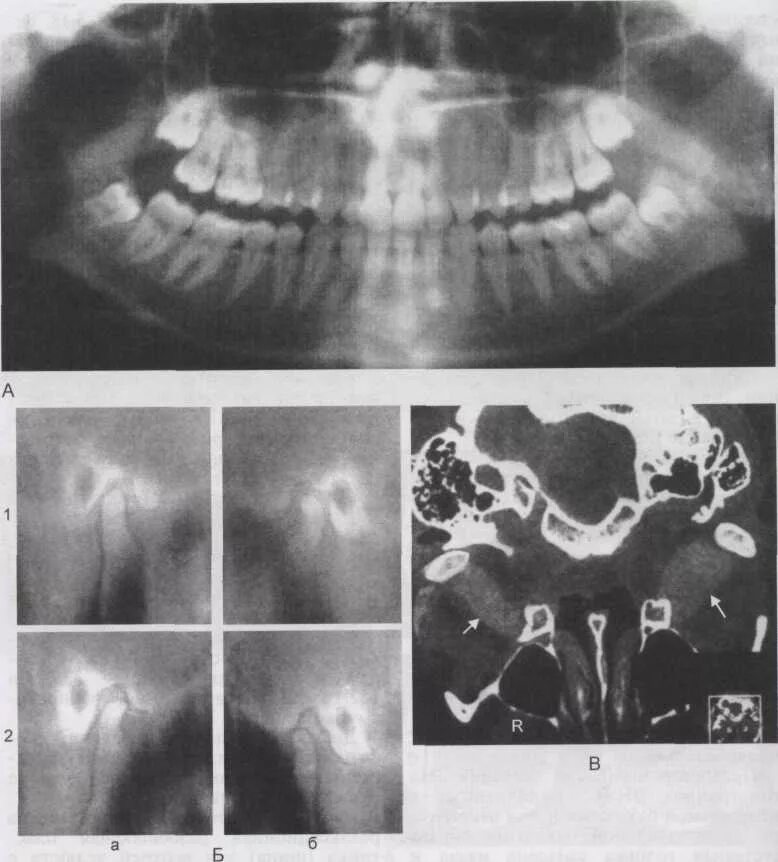

Дислокации дисков